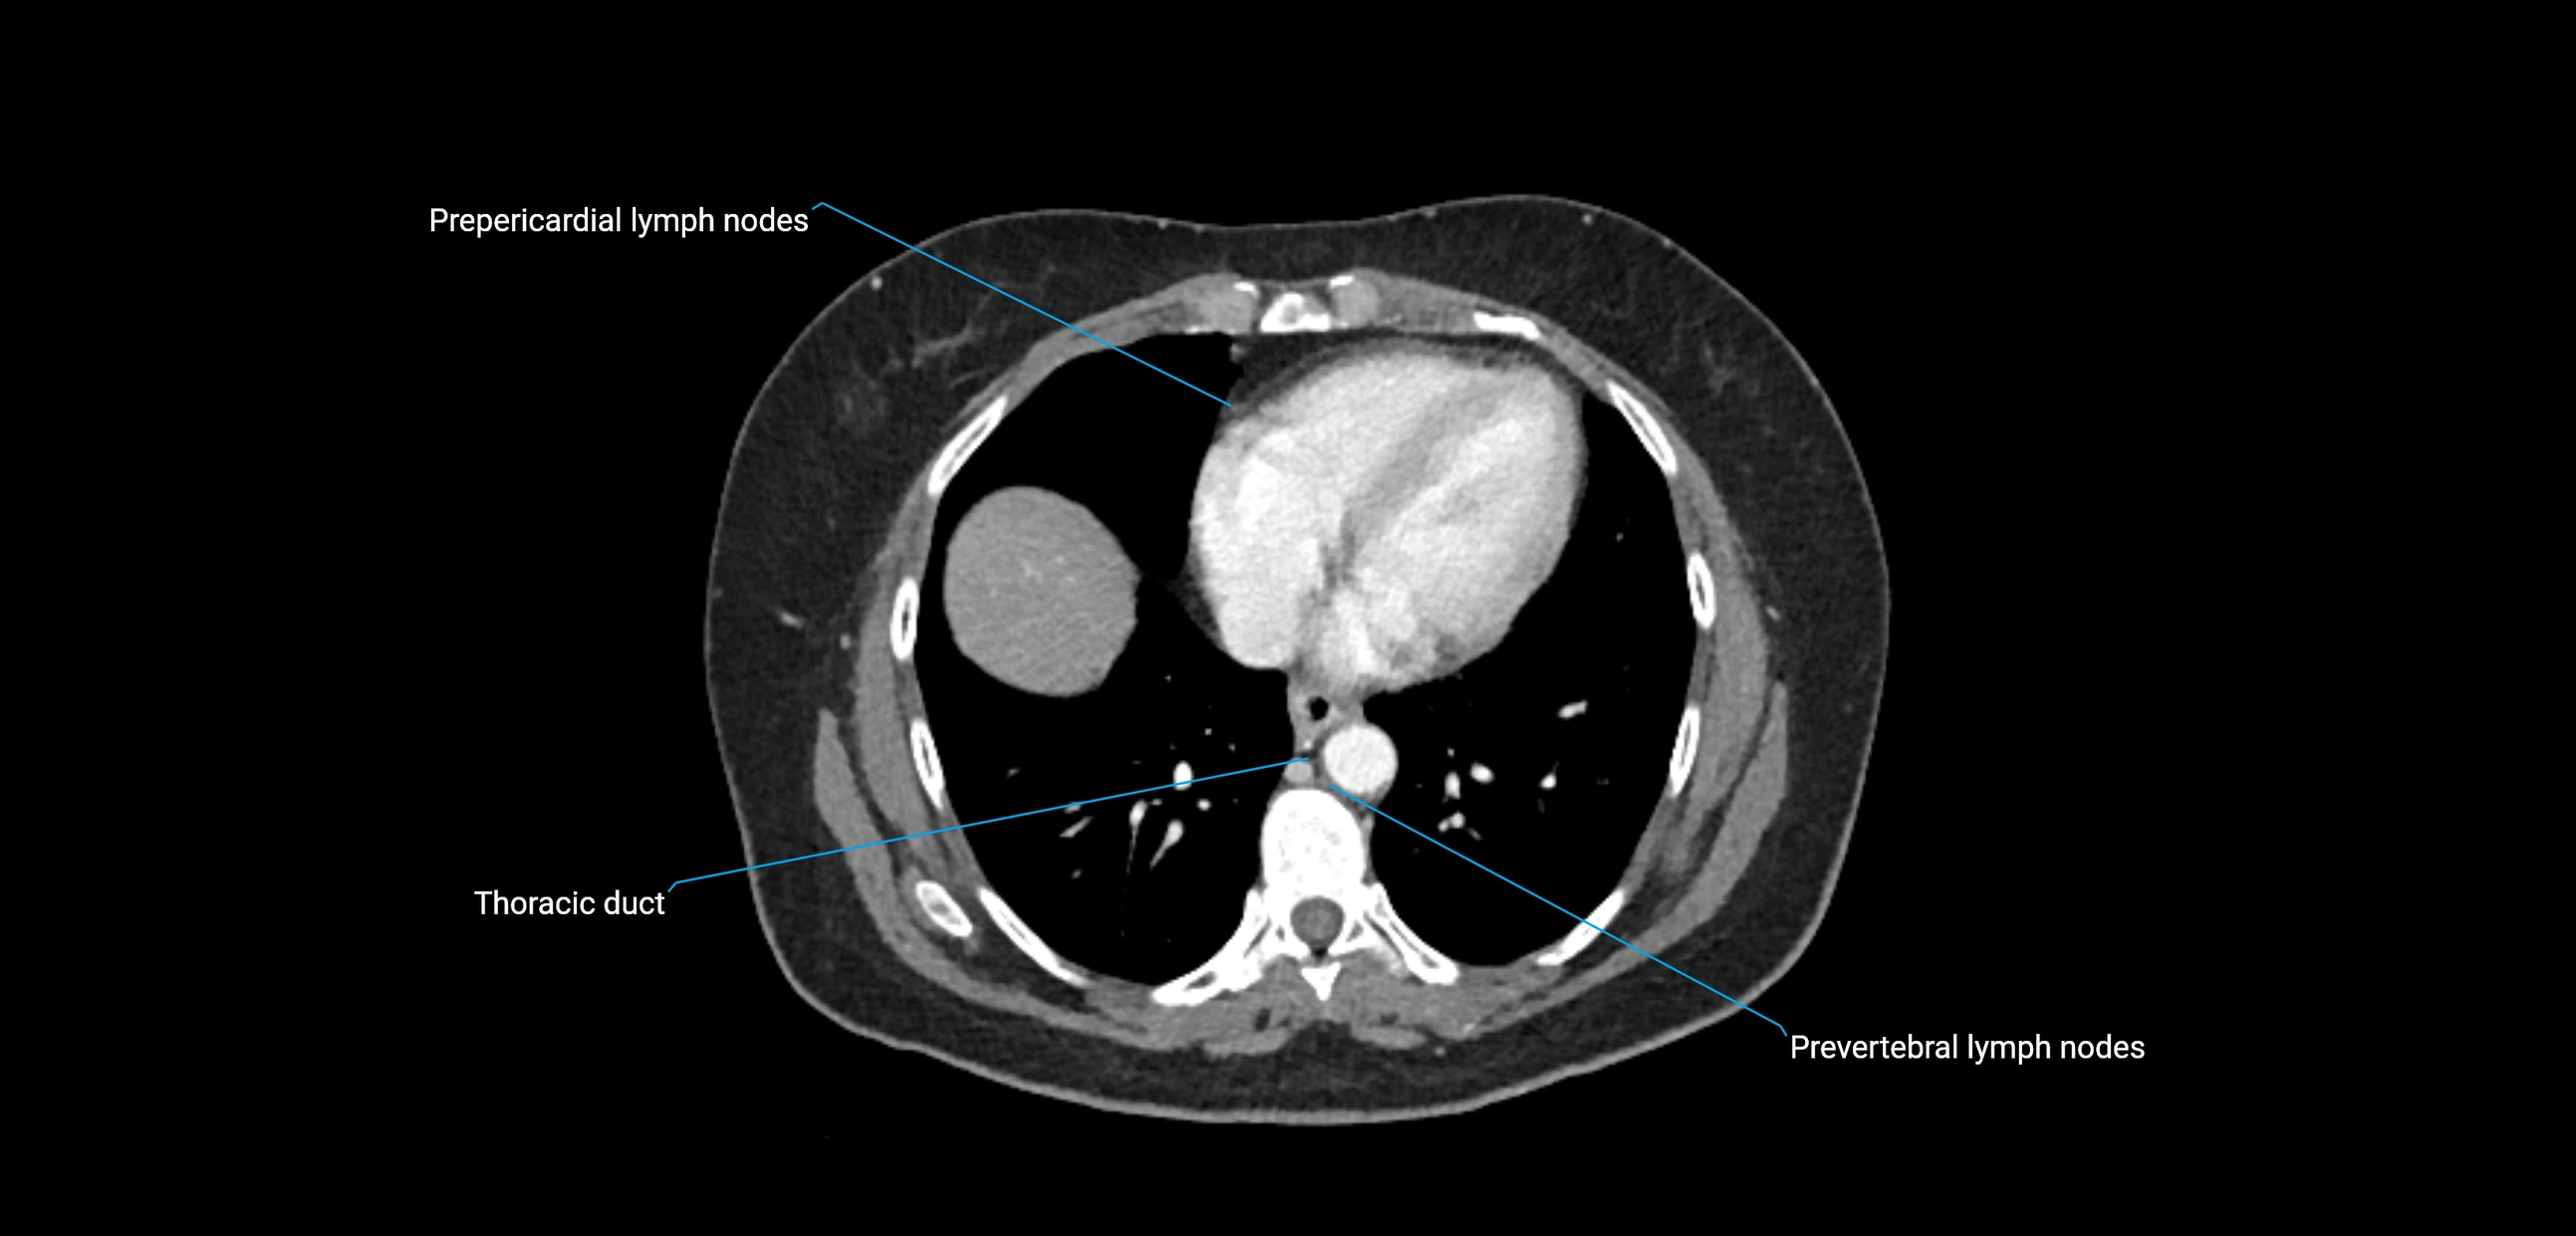

CT Appearance

CT Pre-Contrast:

• Nodes appear as soft-tissue density nodules adjacent to the aorta and IVC

• Calcification may be seen in chronic infections (e.g., tuberculosis)

CT Post-Contrast:

• Normal nodes enhance homogeneously

• Malignant nodes may show heterogeneous enhancement, central necrosis, or conglomerate formation

• Size >1 cm short axis is suspicious, though morphology and distribution are equally important